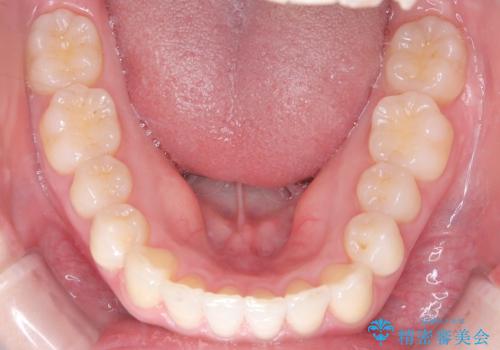

- 左上2の反対咬合(交叉咬合)をインビザラインを用いて治療しました。反対咬合は、歯列の不正咬合の一つであり、上の歯が下の歯よりも内側に位置する状態です。反対咬合は咀嚼や発音に影響を与えることがあります。

左上2の反対咬合をインビザラインで治療する際に、IPR(Interproximal Reduction)を行いました。 IPRとは、隣接する歯の間のエナメル質をわずかに削る手法で、歯の幅を減少させることによって歯列を整える技術です。